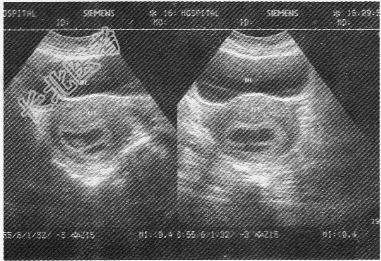

- 单项选择题女性,25岁, 停经46天,阴道无异常分泌物, 超声检查子宫附件如图,图中所示为

A、早期妊娠并宫腔积液

B、子宫肌瘤并早期妊娠

C、双胎妊娠双孕囊

D、正常早期妊娠孕囊及胚外体腔

E、难免流产